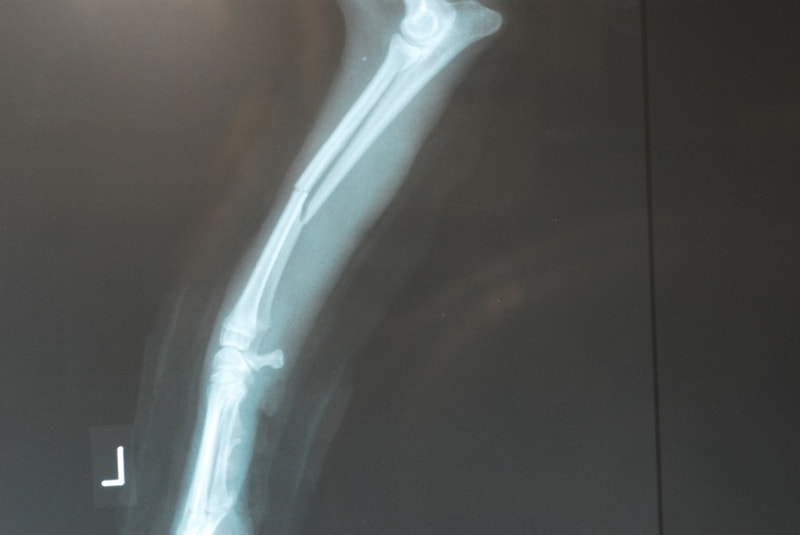

症例3:キルシュナーワイヤーのピンニングによる整復

ペルシャ猫 11ヶ月齢 雄

他院にて左大腿骨遠位の成長板骨折(salter-harrisⅠ型)が認められており、治療相談を目的として来院。当院にて、キルシュナーワイヤーを用いたピンニングにより骨折部位の整復を行いました。術後の経過は良好で、現在も経過観察中です。

術前レントゲン

術後レントゲン